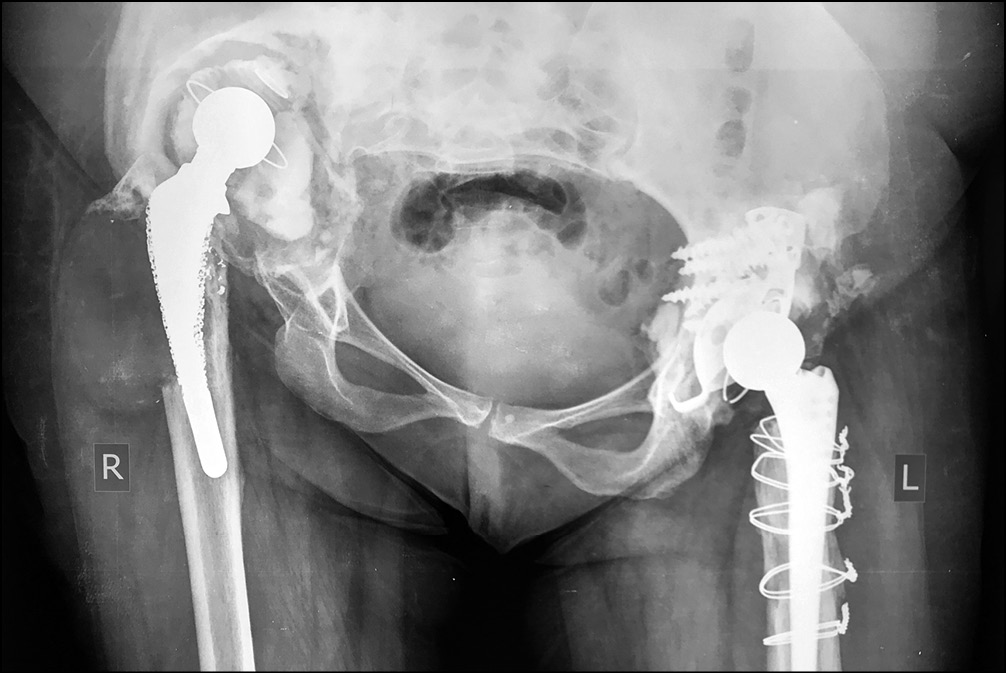

На контрольных рентгенограммах выявлен дефект вертлужной впадины типа IIIA и дефект бедренной кости типа IIIB по классификации W.G. Paprosky. В 2012 г. по поводу нестабильности тотального эндопротеза левого тазобедренного сустава выполнено ревизионное эндопротезирование с использованием антипротрузионного кольца ЭСИ (фирма Эндосервис) с цементной чашкой и бедренного компонента типа Цваймюллера, дефект бедренной кости восстановлен с применением свежезамороженного кортикального трансплантата. (рис. 7 и 8).

Рис. 7. Рентгенограмма таза перед ревизионным эндопротезированием левого тазобедренного сустава в 2012 г.

Рис. 8. Рентгенограмма таза после ревизионного эндопротезирования левого тазобедренного сустава в 2012 г.